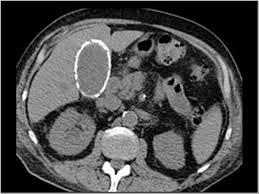

What does this patient have?

Porcelain gallbladder –rimlike calcification in RUQ. This condition occurs with chornic inflammation and stasis and is associated with both gallstones and an increased incidence of gallbladder CA.